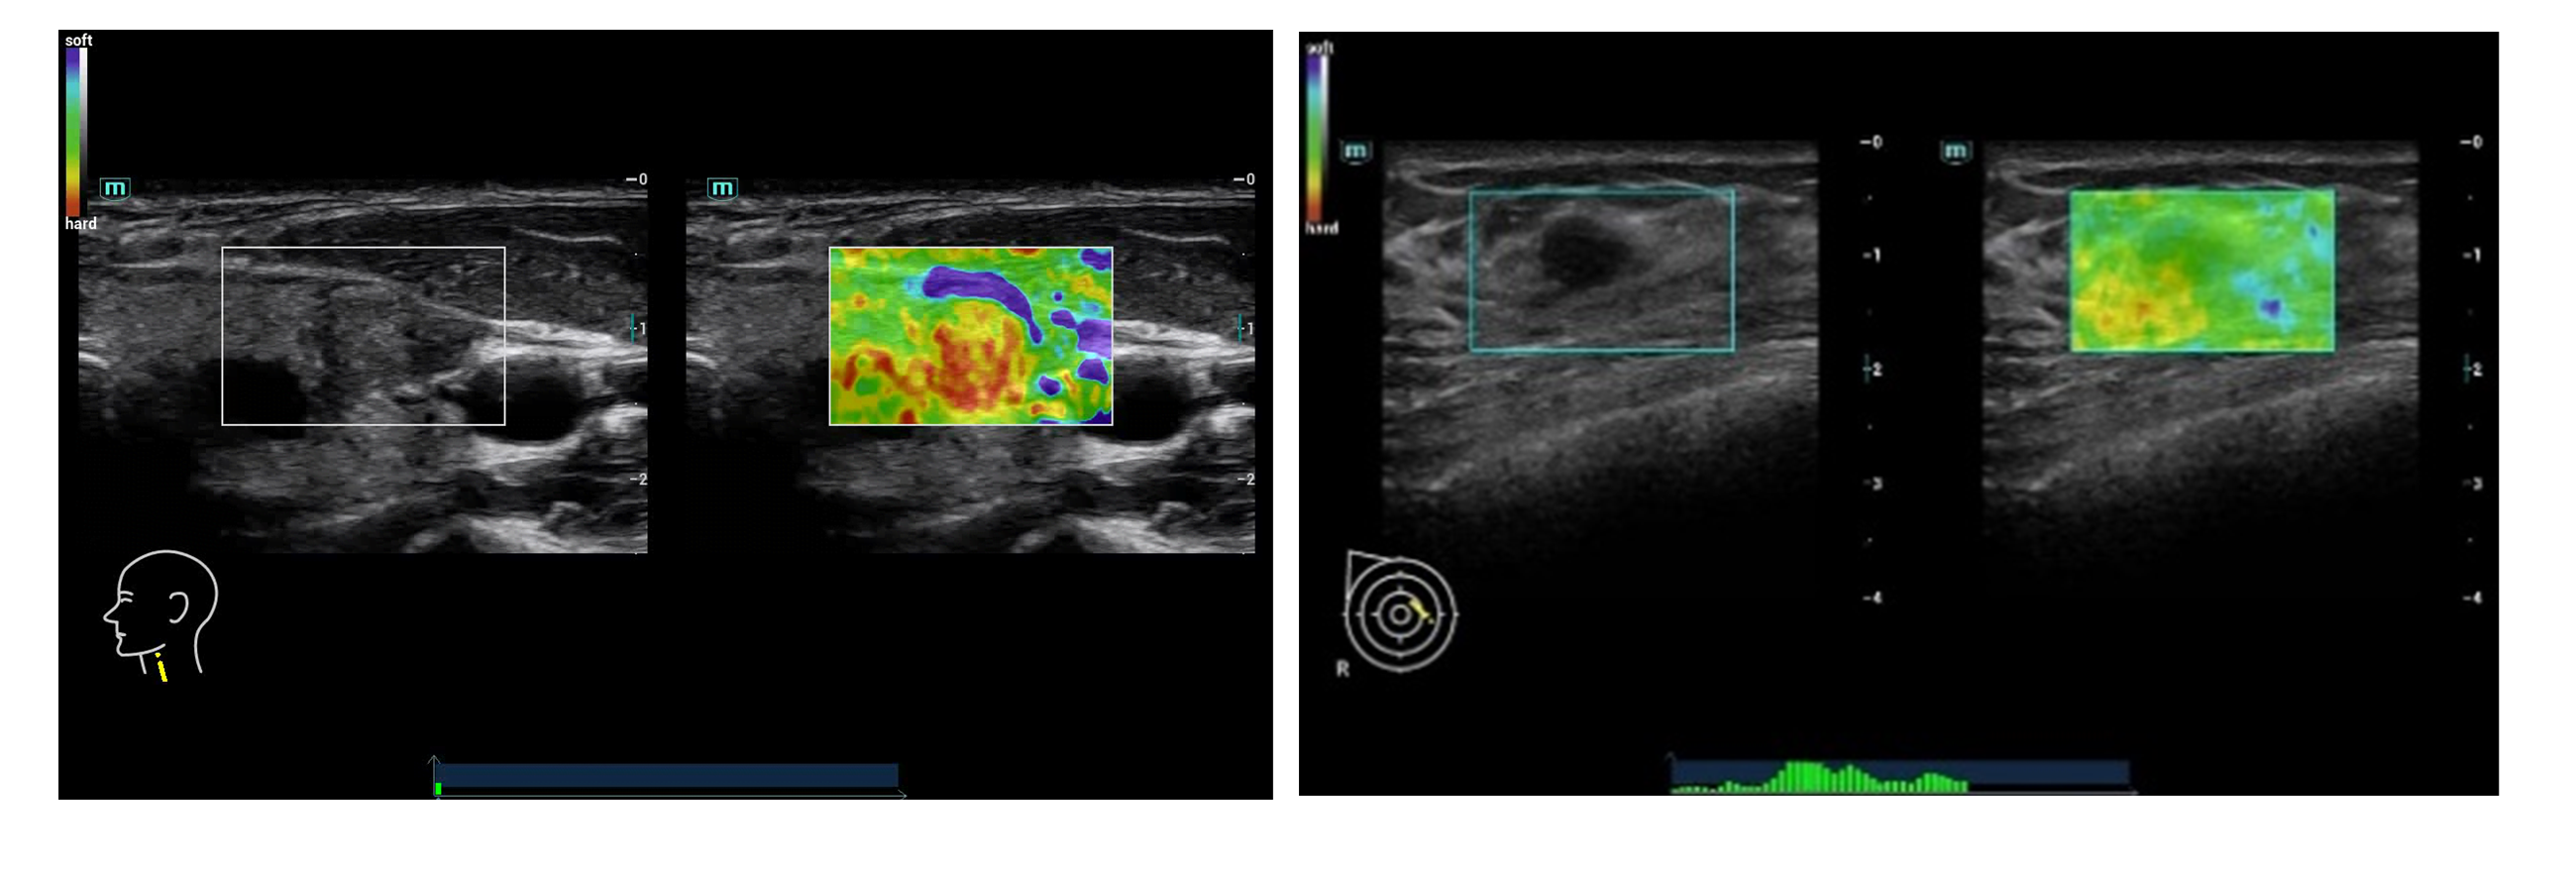

Λογισμικό Ελαστογραφίας STE shearwave Elastography (optional)

Η προσφερόμενη μονάδα υπερήχων παρέχει την πιο σύγχρονη και πρωτοποριακή απεικονιστική τεχνική Shearwave Elastography STE για την μη επεμβατική ιστική μελέτη επιφανειακών και ενδοκοιλιακών οργάνων. Διαθέτει διπλή και ταυτόχρονη απεικόνιση (Real Time) 2D & 2D + ελαστογραφία shearwave με χρωματική κωδικοποίηση των ιστών (προς επιλογή διαφορους ελαστογραφικούς χάρτες). Η μέθοδος χρησιμοποιείται για την μελέτη αλλοιώσεων σε επιφανειακές και εν τω βάθει δομές όπως στον προστάτη, μικρά όργανα άνω κάτω κοιλία κλπ. Η υπερηχογραφική Ελαστογραφία παρέχει στον κλινικό ιατρό πληροφορίες υψηλής ευαισθησίας και ειδικότητας για την ελαστικότητα των ιστών εφοδιάζοντάς τον με πληροφορίες που τον βοηθούν στον χαρακτηρισμό και την κατηγοριοποίηση των ιστολογικών αλλοιώσεων.

NTE (optional)

Σύγχρονη τεχνική ελαστογραφίας για τον διαχωρισμό μεταξύ μαλακών (ελαστικών) και σκληρών (συμπαγών) ιστών, σε κλινικές εφαρμογές μαστού και θυρεοειδούς. Διαθέτει διπλές ταυτόχρονες απεικονίσεις 2D & 2D+ ελαστογραφία με χρωματική κωδικοποίηση των ιστών (8 ελαστογραφικούς χάρτες) σε Real Time (πραγματικό χρόνο). Η μέθοδος Strain elastography NTE Natural touch elastography είναι μέθοδος μέτρησης της ελαστικότητας και της σκληρότητας των ιστών που χρησιμοποιείται για την μελέτη αλλοιώσεων σε επιφανειακές δομές όπως στο μαστό, θυρεοειδή που συσχετίζονται με την αλλαγή της σκληρότητας των ιστών. Η υπερηχογραφική Ελαστογραφία παρέχει στον κλινικό ιατρό πληροφορίες υψηλής ευαισθησίας και ειδικότητας για την ελαστικότητα των ιστών εφοδιάζοντάς τον με πληροφορίες που τον βοηθούν στον χαρακτηρισμό μιας βλάβης, επιλογή μεταξύ διαφορετικών χαρτών και δυνατότητα μετρήσεων STRAIN RATIO MEASUREMENT.